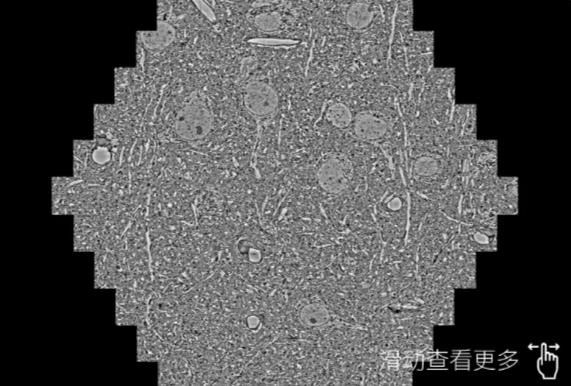

鼠脑切片。左图使用鹤岗蔡司鹤岗扫描电镜MultiSEM706对165μmx143pm面积区域成像,耗时仅需1.5秒。右图为鼠脑切片中30μm区域放大效果。样品由芝加哥大学B.Kasthuri提供。

使用蔡司高速鹤岗扫描电镜MultiSEM对1mm²人脑皮层组织进行高分辨成像,并对其中的各种细胞结构进行三维重构分析。左图展示了2x3mm²组织平面中锥体神经元的三维重构效果。右图显示了局部体积神经元三维重构。图像由哈佛大学chtman实验室提供,渲染图由D. Berger 制作。